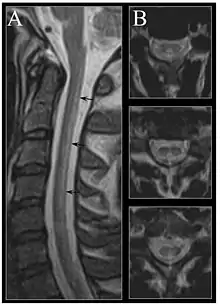

Image of the cervical spinal cord in vitamin B12 deficiency showing subacute combined degeneration. (A) The midsagittal T2 weighted image shows linear hyperintensity in the posterior portion of the cervical tract of the spinal cord (black arrows). (B) Axial T2 weighted images reveal the selective involvement of the posterior columns.

MRI of the brain may show periventricular white matter abnormalities. MRI of the spinal cord may show linear hyperintensity in the posterior portion of the cervical tract of the spinal cord, with selective involvement of the posterior columns.